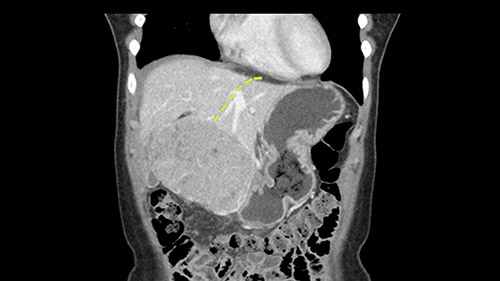

So if we look at the CT scan, on the axial, it’s a larger lesion. It’s about 6 or 7 or 8 centimeters. So it does look a bit threatening in terms of its resectability but if you really drill down deeply into the anatomy, and I think the coronal [imaging] is even better, you can see that the entire mass is on the patient’s left side of the falciform ligament. So it’s really only a left-sided tumor and not even really a left-sided tumor because Segment 4 is uninvolved anatomically.

None of the parenchyma is affected and this tumor is very exophytic; like many Hepatitis B hepatomas; and otherwise is resectable with either a wedge resection part of Segment 2-3 or a formal left lateral segmentectomy.

Some of my colleagues thought it may be involving Segment 4 and we’d need a formal left hepatic lobectomy, dividing anatomically: the left portal vein, left hepatic artery, left bile duct. But I didn’t think so, but you can see there is a challenge in terms of being certain where this tumor is located. So we’re prepared to do any of those 3 but my person view is that its going to be an exophytic tumor off of the left lateral segment and probably a wedge.

So the issue with regards to resection. A left sided tumor. I believe I can see the falciform ligament right here so we’re looking at a resection of Segments 2, 3 of the left lobe of the liver. The left portal vein is right there. I think we’ll be wiser to take the left portal vein and therefore get well into Segment 4 and do a left hemihepatectomy. Certainly, one does not need to take the middle hepatic vein; it’s miles from the tumor.

We note that the tumor is pushing on the gallbladder but I think that’s probably external for the most part. I think that’s extrahepatic. I believe that Segment 4b is probably free of tumor. I’d have to say that it's tempting, particularly looking at the coronals, to consider a very limited resection. Where you’d just chip it off the bottom of Segment 3 and do a limited Segment 3 resection. I’d be concerned about the oncologic margins. I believe that the best oncologic operation will be to take the left portal vein to get this. Certainly, she’s got plenty of liver and she’d be able to sacrifice Segments 2-3 of the left lobe of the liver. It’s not necessary to take too much of thus of Segment 4a. But once one takes the portal vein, that will be compromised. So I would do a left hemihepatectomy on this woman.

The tumor is so close to the falciform ligament, I had a question mark about the Segment 4b relation between segment 4b and segment 3. In a normal resection of segment 2 and 3, we would be keeping on the left side of the falciform ligament and start getting segment 3 and 2 portal pedicles but in here its getting so close. So oncologically, 4b should be checked during the OR.

What kind of procedure can we plan for this patient? It obviously has to be a left hemihepatectomy because most of the lesion is actually in Sg4. Can we do something which is less than a hemihepatectomy and just do only a segmental resection? The answer to that is that this vascular supply, if you are trying to ligate only the portal venous pedicle to the Segment 4, it is very close to the tumor and you will end up not having not a great margin as far as tumor resection is concerned so I would recommend a left hemihepatectomy and not just a partial or segmental resection. You can also see that it is crossing the falciform line and going on to Segment 2 and 3 so trying to do anything less than a left hemihepatectomy may not give the right kind of margins which we need for this tumor. Fortunately for us, the contours of the liver, which are very important to see in a Hepatitis B patient, there are no cirrhosis which I can see. The normal liver functions indicate that it's a well compensated Hepatitis B.

The other thing I would do in this case is to certainly to assess the coronal phase as we can see in the coronal phase, this tumor looks like it's growing from Segment 3, and again I don’t think there’s involvement of the right side of the liver or even on Segment 4.

So in terms of planning on the surgery, I think there’s two clear options for this patient and that we’ll need to assess once we’re in the operating room. One option would be to do a Segment 3 resection. This tumor seems like it's hanging from Segment 3 so I think if we can get a good margin, that would be an option. Of course the other option is to do a left hepatectomy, preserving the middle hepatic vein, which is clearly not involved with the tumor.